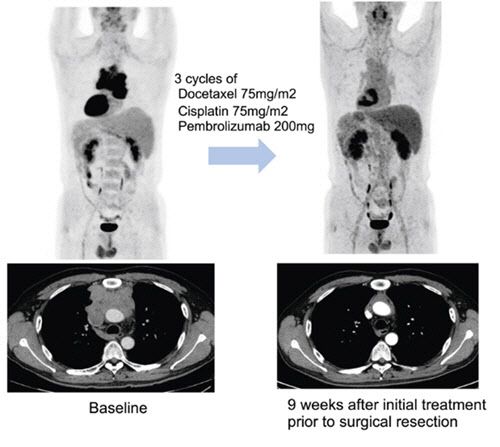

연구팀은 이들 환자에게 3주 간격으로 세 번에 걸쳐 기존 항암화학요법에 펨브롤리주맙을 병용 투여한 다음 수술 가능 여부를 평가했다. 수술 후에는 최대 32주간 펨브롤리주맙 유지하는 한편, 일부는 항암방사선치료를 더하는 식으로 치료가 진행됐다.

연구팀은 추적관찰 기간 27.5개월(중앙값) 동안 전체 환자의 57.5%(23명)에서 수술 전 치료를 통해 종양의 크기가 유의미하게 감소하는 반응을 보였다고 했다. 또한 82.5% 환자에서는 해당 치료로 인해 질병의 진행이 억제 되는 질병 조절이 관찰됐다고 전했다.

수술을 받을 만큼 암이 줄거나 반응을 보인 덕분에 전체 환자의 70%(28명)가 수술을 받았다고 밝혔다. 치료 결과 병리 검사를 통해 암세포가 10% 이하로 감소한 지를 평가(MPR)했을 때 전체 환자의 32.5%(13명)가 도달한 것으로 나타났다. 당초 기대치 50%에는 미치지 못했지만, 수술 환자 놓고 보면 MPR 도달 비율은 46.4%로 증가해 펨브롤리주맙이 흉선상피종양 치료 선택지에 포함될 가능성에 파란불이 켜졌다.